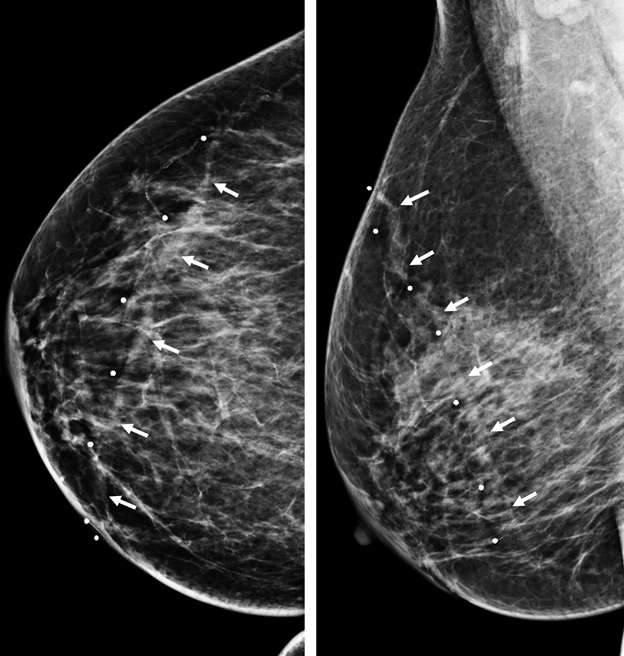

Superficial thrombophlebitis of the breast, or Mondor disease, is a superficial veno-occlusive disease most commonly involving the thoracoepigastric, lateral thoracic, or superior epigastric veins of the upper outer or upper inner quadrants, or inferior breast and chest wall. The clinical presentation varies with acuity, ranging from incidental and asymptomatic, to a focally painful palpable “cord” with associated yellowish or purplish skin discoloration and/or skin retraction or dimpling. The condition most often affects women in their third to sixth decade of life (75%) but can also occur in men. Causative factors are shared with other common causes of thrombophlebitis outside of the breast, and include trauma, post biopsy/surgery, botulinum toxin or other injections, pregnancy, breast cancer, and other hypercoagulable states. However, the majority of cases of Mondor disease are idiopathic. Ultrasound is the gold standard in diagnosis, which classically shows a noncompressible hypo- or anechoic superficial tubular or beaded structure, occasionally with demonstrable wall thickening and inflammatory changes (Figure 3A-B). Color Doppler shows minimal to no flow. Chronic thrombosis may result in vascular calcification, which may be seen as hyperechoic intraluminal foci with posterior shadowing or comet tail artifact. The disease course is often self-limited, with most cases resolving spontaneously over 2-12 weeks. Treatment is supportive with over-the-counter analgesics (e.g., ibuprofen, acetaminophen) as needed for pain. Importantly, there is no role for antibiotics or anticoagulation therapy, as Mondor disease is not infectious in origin and by definition does not involve the deep venous system.